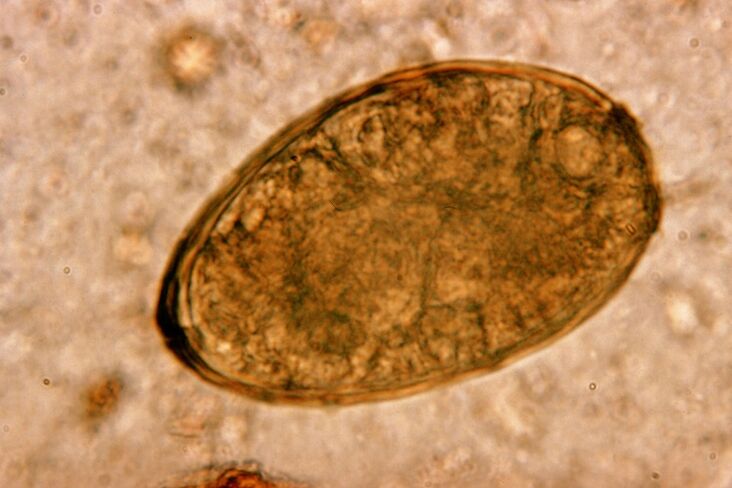

Roundworms, roundworms, live and reproduce in the intestines.Their infection occurs through eggs that enter the body on food or on hands and objects used by an infected person.Soil, fruits, vegetables, undercooked meat and fish – all of these can introduce worm eggs into the body.

Worth knowing!Roundworms can cause a dry cough.Their larvae migrate through the circulatory system and enter the respiratory organs - bronchi, trachea, lungs - irritating receptors and causing this symptom.The migration period of the larvae throughout the body lasts one to two weeks.

Roundworms are so common that coughing due to ascariasis is a typical symptom.Roundworm infection occurs through the traditional route of helminthiasis.These include contact with soil, eating unwashed fruits and vegetables, and dirty hands.

Roundworm larvae cause problems by mechanically affecting respiratory tissue.This occurs during the migratory stage of the parasite.The mechanism and sequence of the effects of roundworms on the human respiratory system are as follows.

Once in the gastrointestinal tract, the roundworm eggs shed their shells and transform into larvae under the influence of their own enzymes and digestive juices.The latter has the ability to penetrate the intestinal wall and enter the bloodstream.They are then carried throughout the body by the bloodstream - reaching the liver, heart, lungs and respiratory tract.